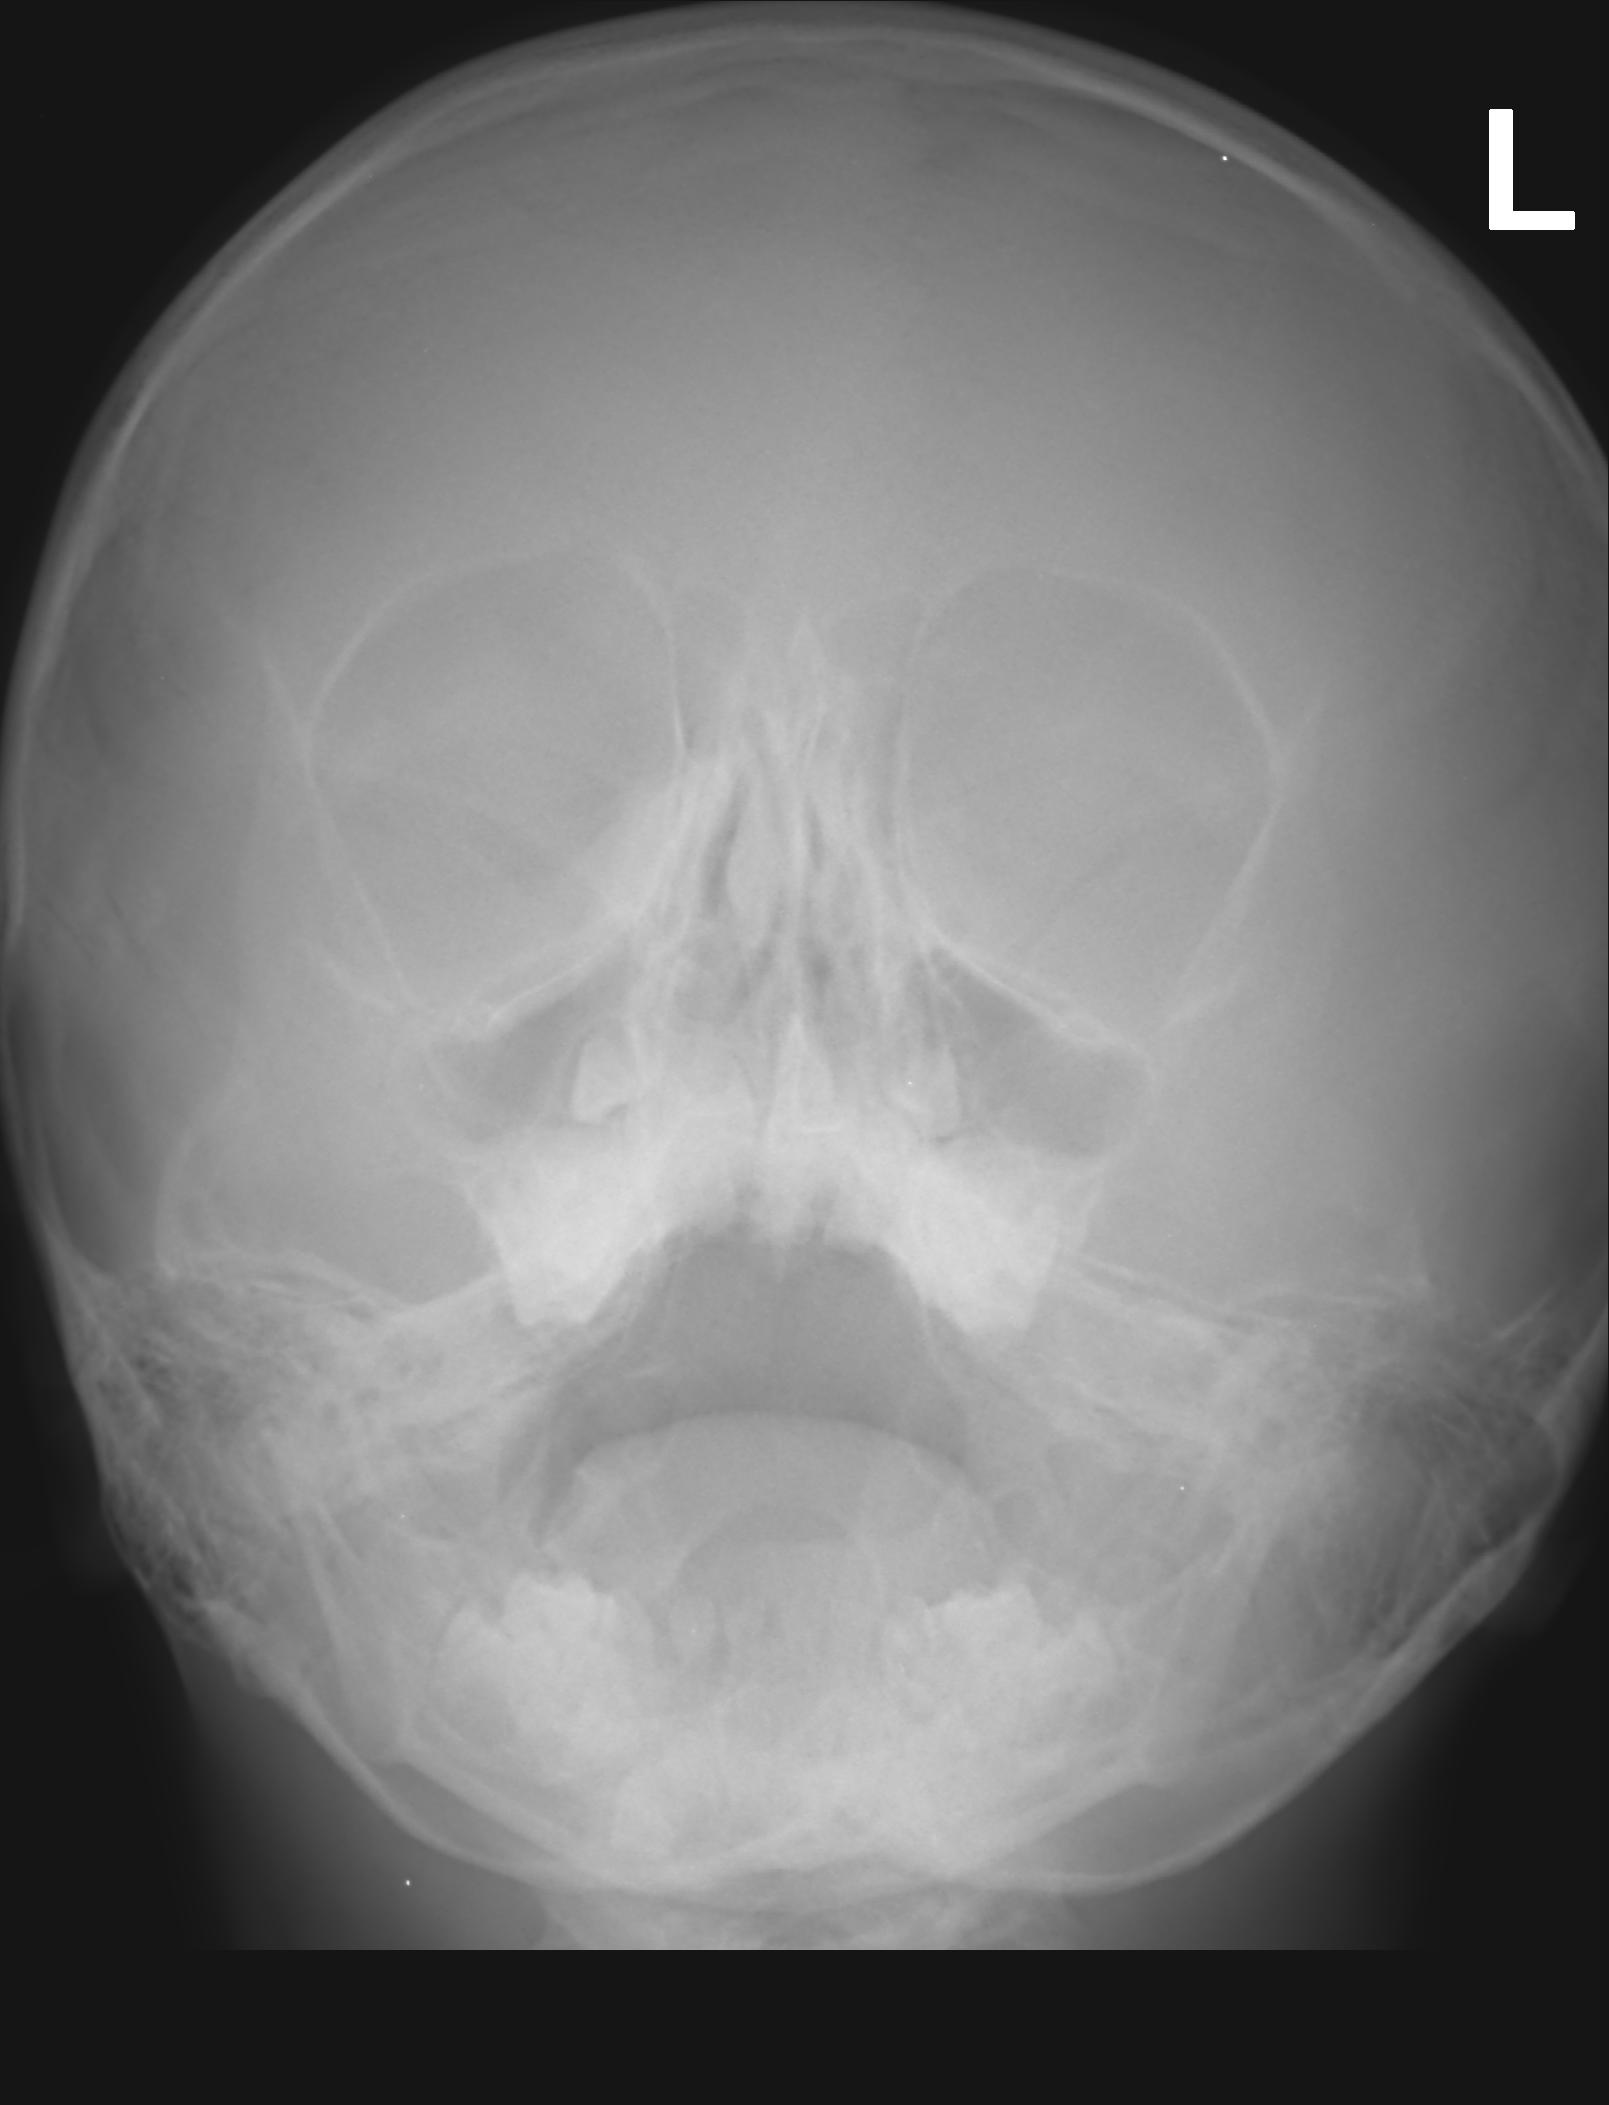

Здравейте имам момче на 5 години, което боледува много и често. Като по малък правеше много често разстройства с вискока температура, което премина след третата година, след това От всяка хрема става усложнение бронхит, пневмония и синузит, с много продължителна и мъчителана кашлица, въпреки че веднага ходим на лекар.Калицата в повечето случай е влажна и отделя храчки с продължителност около 3 седмици, след оздравяването не остава кашлица която да продължи. В всички боледувания се назначава антибиотик минимум за 10 дни и инхалаций с пулмикорт и вентолин.На база ПКк с завишени левкоцити и след лечението ПКК в норма.Като няколко пъти се наблюдава след спиране на пулмикорт , кашлицата се засилва. От няколко специалиста в областа, категорично беше отхвърлено да има данни за муковизцидоза.Наскоро е правно изследване за клостридиум токсин А и Б (-) отрицателен и панкреатитна еластаза в норма. Детето е на 5 години и 3 месеца, висок е 116 см и тежи 26 килограма. Водила съм го на три специалиста уши, нос и гърло. Няма данни за уголемена трета сливица, но има изкривена носна преграда. Преди време бяха изолирани стафилокои и стрептококи пневмоние ( силно резистентна).Като на антибиграма излиза антибиотик който го няма за неговота възраст. Който в последствие уж са изчистени.Казвам уж, защото са взимани 13 пъти секрет от носа и гърлото в различни лабораторий и само веднъж излезе с бактерия. Бях ме и при трима детски пулмулози, който бяха на коренно различни мнения. Някой изказваха съмнение за алергична астма и за неуточнена астма. Правени са кръвни изследвания в лаборатория Геника всички възможни панели никъде няма отклонения. Тестван е за алергии при два алерголози , пак няма данни за алергии. В семейството няма алергични. Правени са снимки на бял дроб няколко пъти и на синусите няколко пъти. Приема ли сме много и различни видове витамини, имуностимулатори и имуностимуланти. Като нещата се влошиха след курс на Бронховаксом.Като не знам дали е съвпадение или следствие. Водим го на физиотерапия първо за лечение на синузит , прилагам две снимки на синусите преди и след лечението,и в последствие за профилактика. Изписана му е ефира , приема я вече 2 години без прекъсване, без да се наблюдават странични ефекти и инхалаций с пулмикорт всяка вечер по една за 5 месеца с оглед на факта , че основен провокатор на пристъпите са вирусни инфекции на ГДП. Притеснява ме главно този дълъг прием на Ефира и инхалацийте , да не му навредят повече от колкото да му помагат, как смятате в случай да ги продължавам ли или да ги намалям или да ги спра ? В последните няколко месеца нещата са добре и не е боледувал.

- Преди проведено лечение

- IS01_001.jpg (185.25 KiB) Прегледано 483 пъти